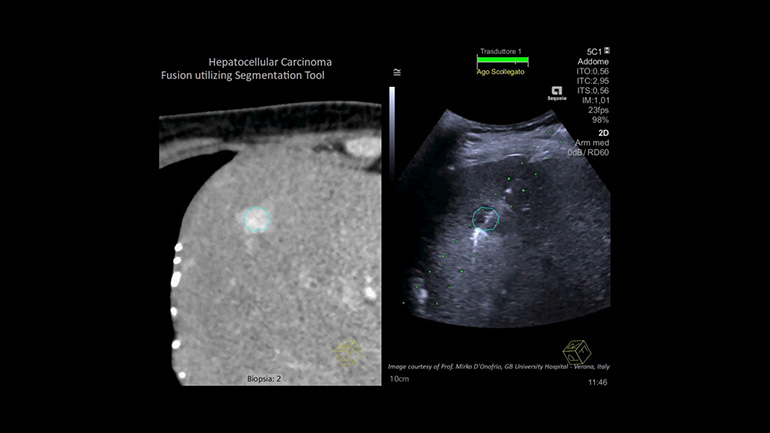

Технология суммации изображений

Эта технология в реальном режиме времени позволяет суммировать УЗ-изображения с диагностическими изображениями, полученные при использовании других диагностических методов визуализации (КТ, МРТ к примеру) для повышения надежности визуализации при сложных интервенционных процедурах.

Технология Fusion Эта технология позволяет суммировать изображения, полученные при работе с разными диагностическими модальностями для повышения надежности визуализации при сложных интервенционных процедурах.

Etrax Технология наведения биопсийной иглы Etrax позволяет отслеживать положение кончика иглы и повышает надежность нацеливания на труднодоступные поражения при сложных интервенционных процедурах.